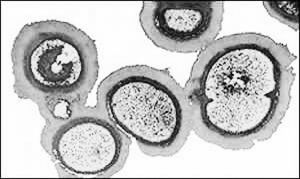

腸道菌群人的胃腸道內寄居著種類繁多的微生物,這些微生物稱為腸道菌群。腸道菌群按一定的比例組合,各菌間互相制約,互相依存,在質和量上形成一種生態平衡。

健康人的胃腸道內寄居著種類繁多的微生物,這些微生物稱為腸道菌群。在人類胃腸道內的細菌可構成一個巨大而複雜的生態系統,一個人結腸內就有400個以上的菌種。